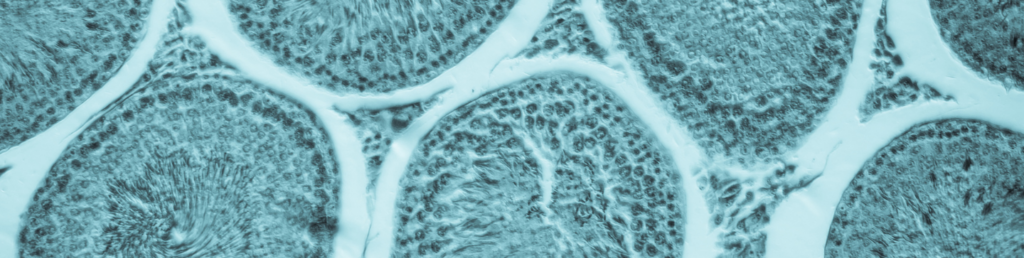

- Fertility and Early Embryonic Development (FEED) study (Segment I) evaluates the effects on mating, estrous cyclicity, spermatogenesis, and ability to produce a viable implant. At Frontage, we assess sperm count, motility, and morphology are assessed using a Hamilton-Thorne Analyzer.

- Embryofetal Development (EFD) study (Segment II) demonstrates the effects of gestational exposure on the pregnant female and the developing fetus during the organogenesis period. This study evaluates fetal development and survival.